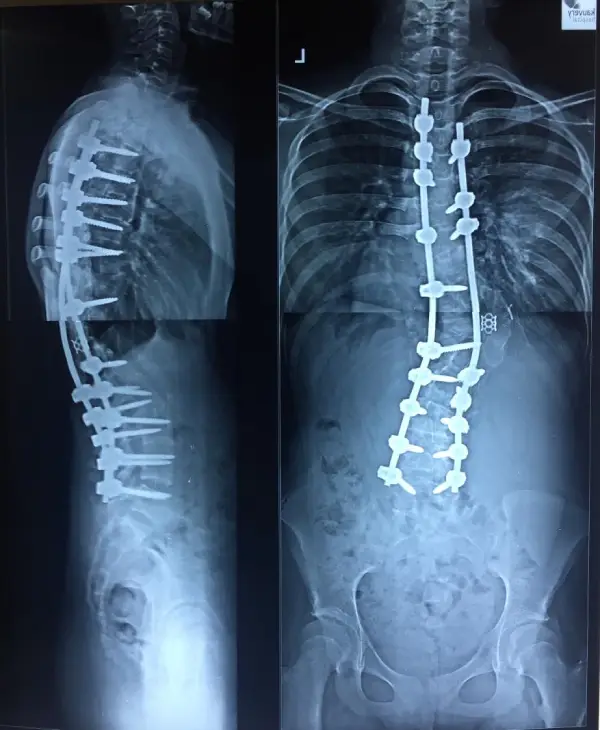

67 years old female presented with the complaints of low back ache radiating to posterior aspect of thigh for past 1 year. History of urinary incontinence (+) for the past 6 months & symptoms worsened for the past 2 months. She had difficulty in sitting, standing and walking on her own, and was totally dependent on care giver.

Diagnosis: Degenerative scoliosis

Treatment: D11 to L5 instrumented deformity correction, decompression and fusion.

Outcome: Patient was started on osteoporosis medications and has significant relief from leg symptoms. She is now an independent woman taking care of her activities of daily living.